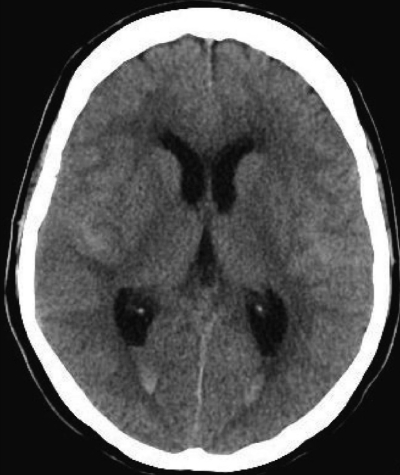

血液所見:赤血球 362 万、Hb 11.2 g/dL、Ht 44 %、白血球 9,800(桿状核好中球 12 %、分葉核好中球 46 %、好酸球 1 %、好塩基球 1 %、単球 2 %、リンパ球 38 %)、血小板 21 万。血液生化学所見:総蛋白 7.5 g/dL、アルブミン 4.8 g/dL、尿素窒素 9 mg/dL、クレアチニン 0.6 mg/dL。CRP 3.4 mg/dL。頭部CTを示す。